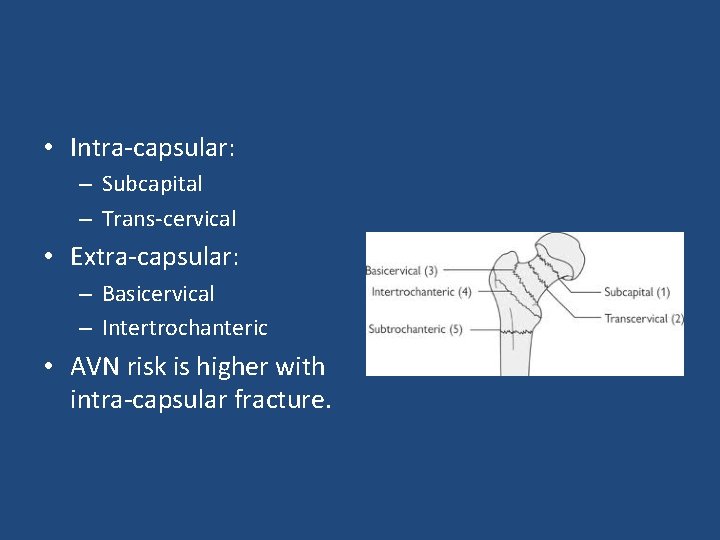

• Fractures can be classified – Intra-capsular – Extra-capsular – Displaced vs not displaced

• Intra-capsular: – Subcapital – Trans-cervical • Extra-capsular: – Basicervical – Intertrochanteric • AVN risk is higher with intra-capsular fracture.